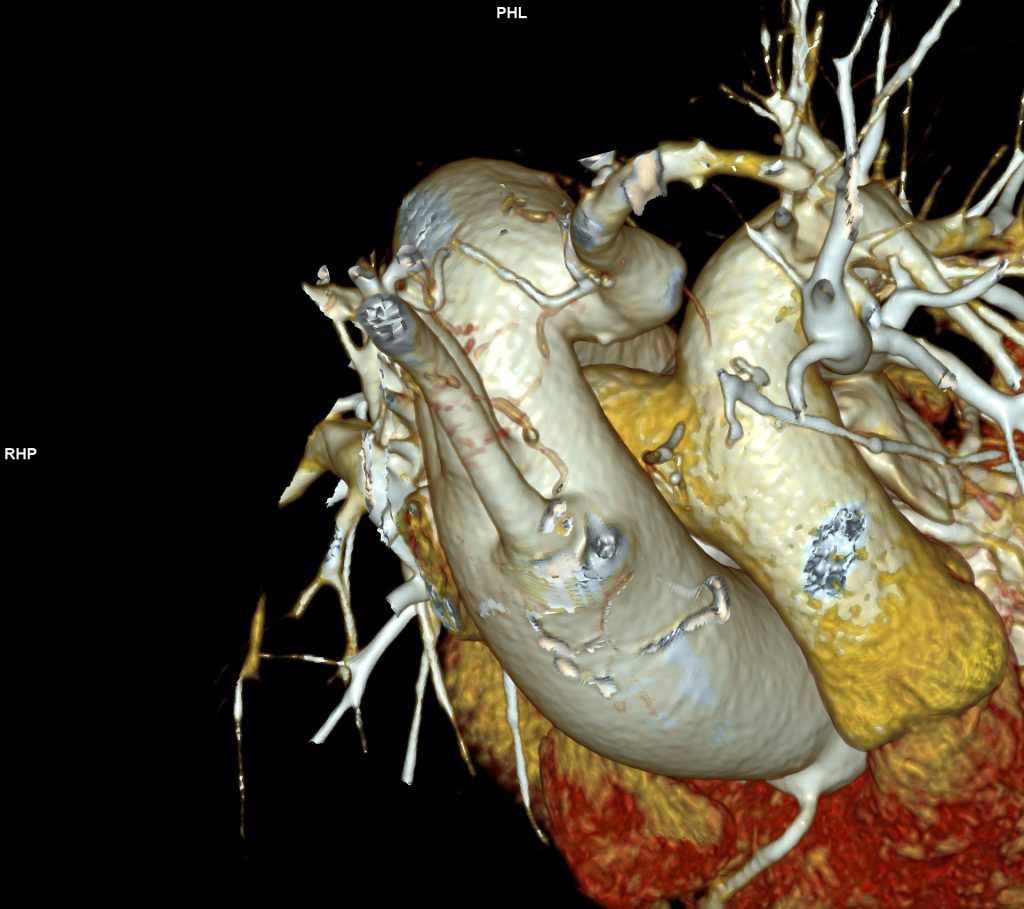

CAZ nr 57: Arc aortic de partea dreaptă si diverticul Kommerell

Figura 3, 4, 5: reconstrucție de volum 3D din achiziție angioCT toracică